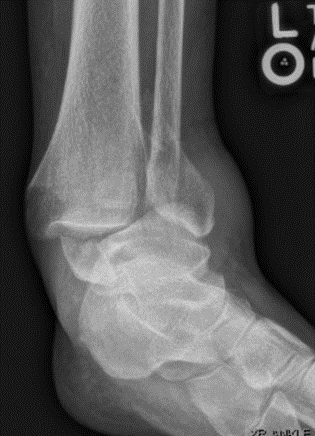

Diagnosis of an ankle injury begins with a physical examination and is usually followed by an X-ray and possibly a CT scan for a more detailed view. Without a radiologic study such as an x-ray or CT scan, it may be difficult to differentiate a broken ankle bone from other conditions such as a sprain, dislocation, or tendon injury. Depending on the nature of the injury, the physical examination may include a “stress test” which evaluates the stability of a suspected ankle fracture, which, in turn, may determine whether surgery is necessary. In complex cases, a detailed evaluation of supporting ligaments through an MRI scan may be recommended.

Ankle Fracture-3 Ankle Fracture-2With non-surgical treatment, the ankle bone is realigned, and a plaster splint is placed around the joint, for at least 2-3 weeks. With surgical treatment, the fractured bone is usually accessed by making an incision over the ankle and then the broken pieces are aligned and compressed together. The bones are fixated with screws and usually, a metal plate is then placed on top for added protection and support. The incision is then sutured closed, and the ankle is immobilized with a splint.